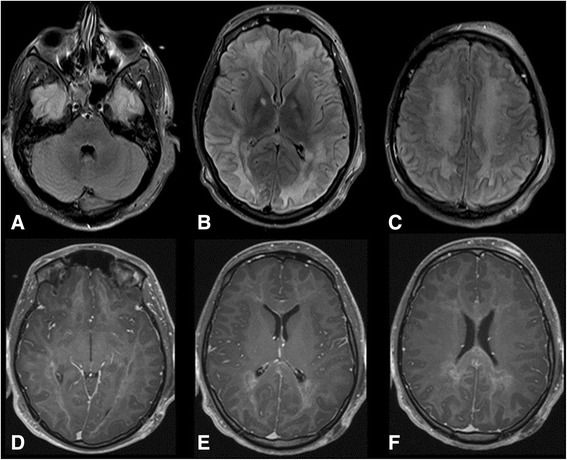

In the fifth day of admission, he was found to have fixed dilated left pupil and normal reactive right one. His level of consciousness was the same. Physical examination showed generalized hypotonia with bilateral extensor plantar responses. Intravenous mannitol was given and urgent CT scan of the brain showed a clear generalized diffuse hypodensity involving the subcortical white matter (Figure 1B). MRI brain done in the 7th day of admission which showed diffuse white matter changes with sparing of the brain stem and cerebellum (Figures 2 and 3).

The MRI findings in our case shows extensive selective white matter damage with sparing of the gray matter. Strikingly, the brainstem and cerebellum were totally spared. Such findings resemble the cases of delayed post hypoxic leukoencephalopathy related to carbon monoxide or opioids overdose. The findings were more pronounced in the diffusion MRI sequences which suggest an acuteness of the illness.

The characteristic MRI findings in DPHL include diffuse white matter hyperintensities on T2 sequences involving the periventricular white matter bilaterally which is diffuse and involves bilateral centrum semiovale areas [ref. 10,ref. 11,ref. 20]. Classically, in cases of DPHL, these lesions are restricted to the periventricular subcortical white matter, sparing the cerebellum or the brain stem [ref. 4,ref. 6,ref. 7,ref. 13,ref. 16,ref. 19] and doesn’t enhance after contrast administration. On diffusion weighted imaging (DWI), there is a symmetric decrease in the apparent diffusion coefficient (ADC) values in the corona radiata and the centrum semiovale white matter [ref. 15]. In addition to areas of restricted water diffusion in both globus pallidi which are usually evident as hypodensities in CT scan [ref. 4]. DPHL Cases caused by carbon monoxide poisoning had also the same involvement of periventricular white matter, centrum semiovale and also sparing of the infratentorial structures [ref. 2]. This finding might help in differentiating DPHL from the chronic heroin vapor inhalation leukoencephalopathy (chasing-the-dragon toxicity) where there is usually involvement of the infratentorial structures, mainly brainstem and cerebellum [ref. 4,ref. 21].